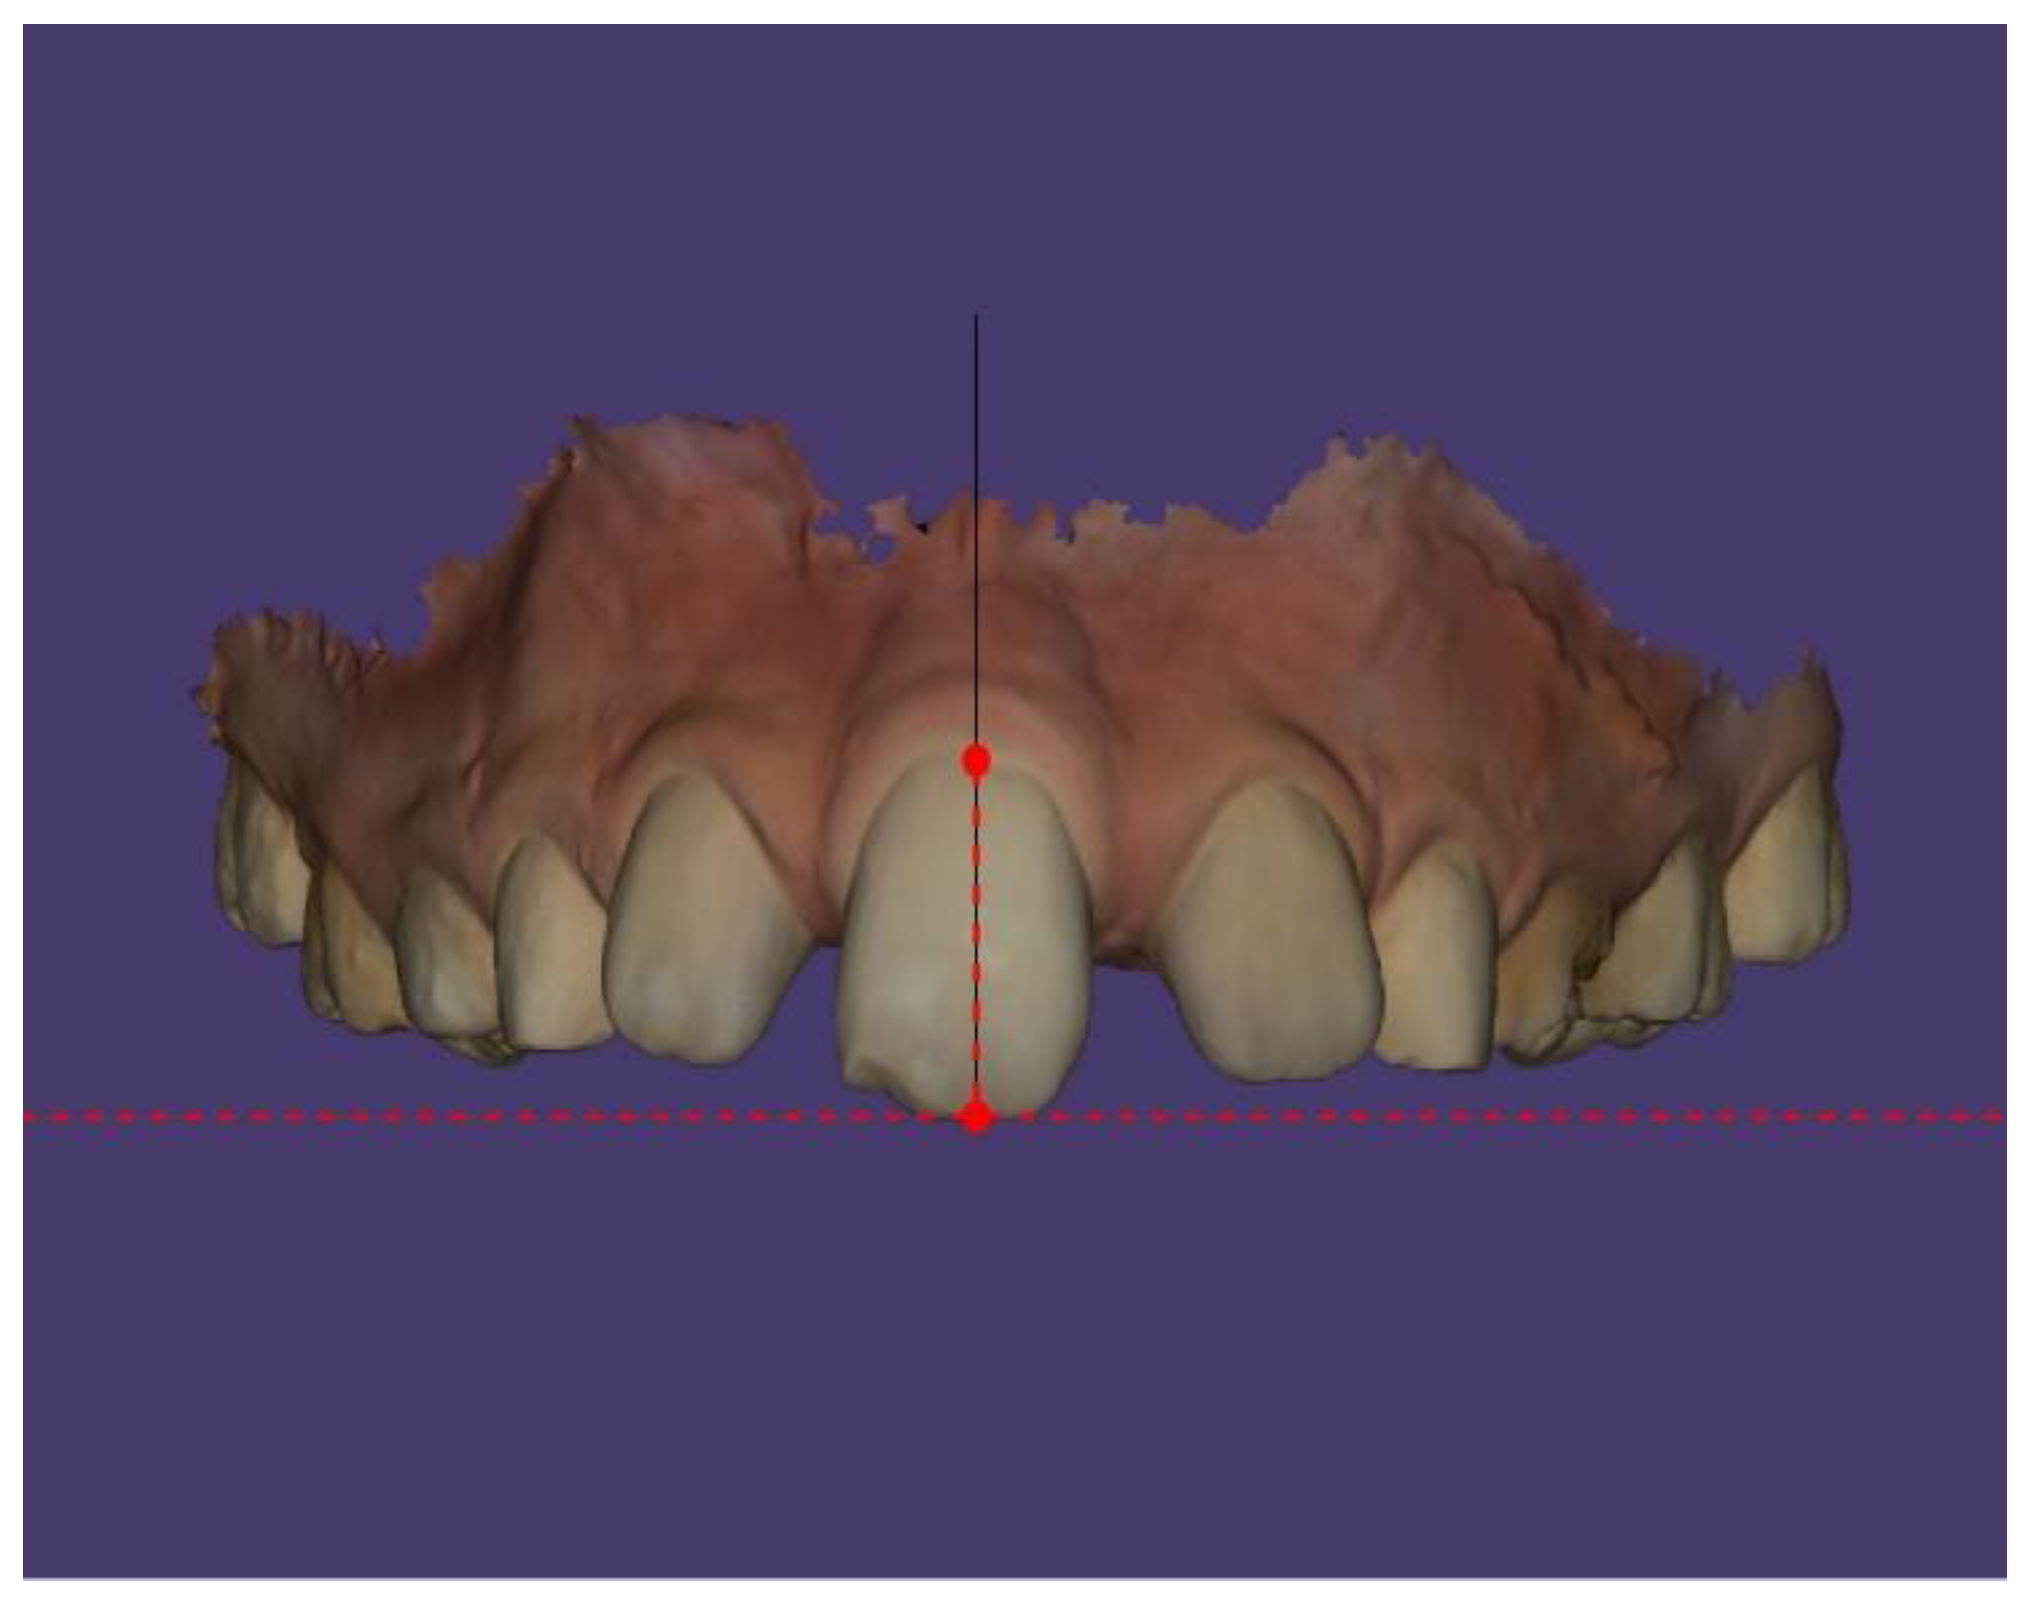

Case Description